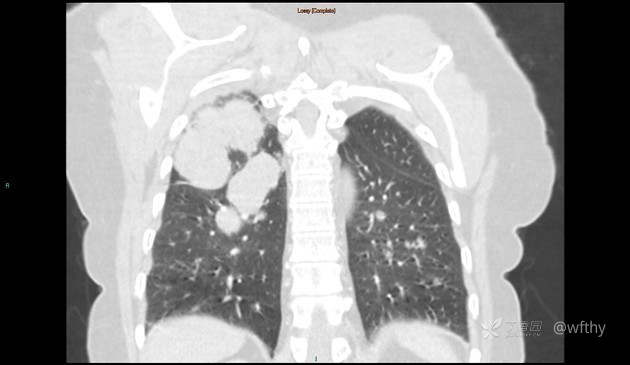

病例女65,头部肿块